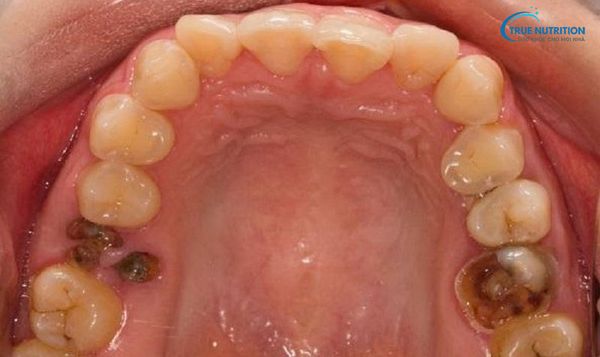

Giai đoạn 4: Răng vỡ hoàn toàn, chỉ còn chân răng

Ở giai đoạn cuối, thân răng bị phá hủy hoàn toàn, chỉ còn lại chân răng nằm trong xương hàm. Đây là hậu quả nghiêm trọng, gây mất chức năng nhai và ảnh hưởng xấu đến sức khỏe toàn thân.

Vết nứt lớn hoặc lỗ sâu rõ ràng: Bề mặt răng bị mẻ hoặc mất hoàn toàn, chỉ còn lại phần chân răng trong nướu.